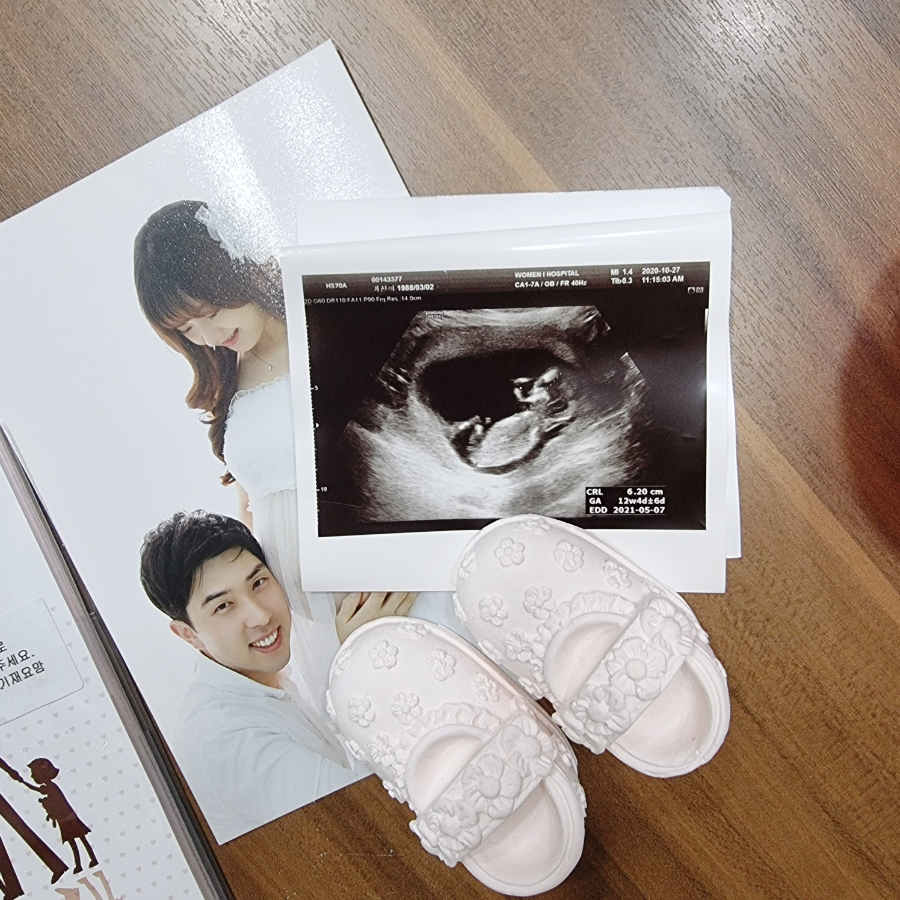

임신 4개월 12주차 초음파 사진입니다.머리의 몸체와 손발이 보이고 손톱이나 손톱도 자라는 시기입니다.심장박동음은 정상! 태아는 원래 심장이 빨리 뛰는게 정상입니다:) 제대가 정상적인 상태인지도 알 수 있습니다.

CRL: 태아의 머리에서 엉덩이까지의 길이, 태아의 크기는 6.2cm로 주수는 12주에 4일 정도, 민낯은 정말 평균 주수대로 커졌습니다.예정일은 5월 7일이라고 적혀있고 실제로 생얼은 1박 2일 유도분만 하고 5월 12일에 태어났습니다.

임신 11주 12주의 초음파 사진인데, 무엇을 찍었는지 잘 모르겠습니다.머리 같기도 하고 배 같기도 하고, 어쨌든 우리의 민낯 목둘레는 3mm 미만이고 목둘레 길이도 정상이라고 하더군요!